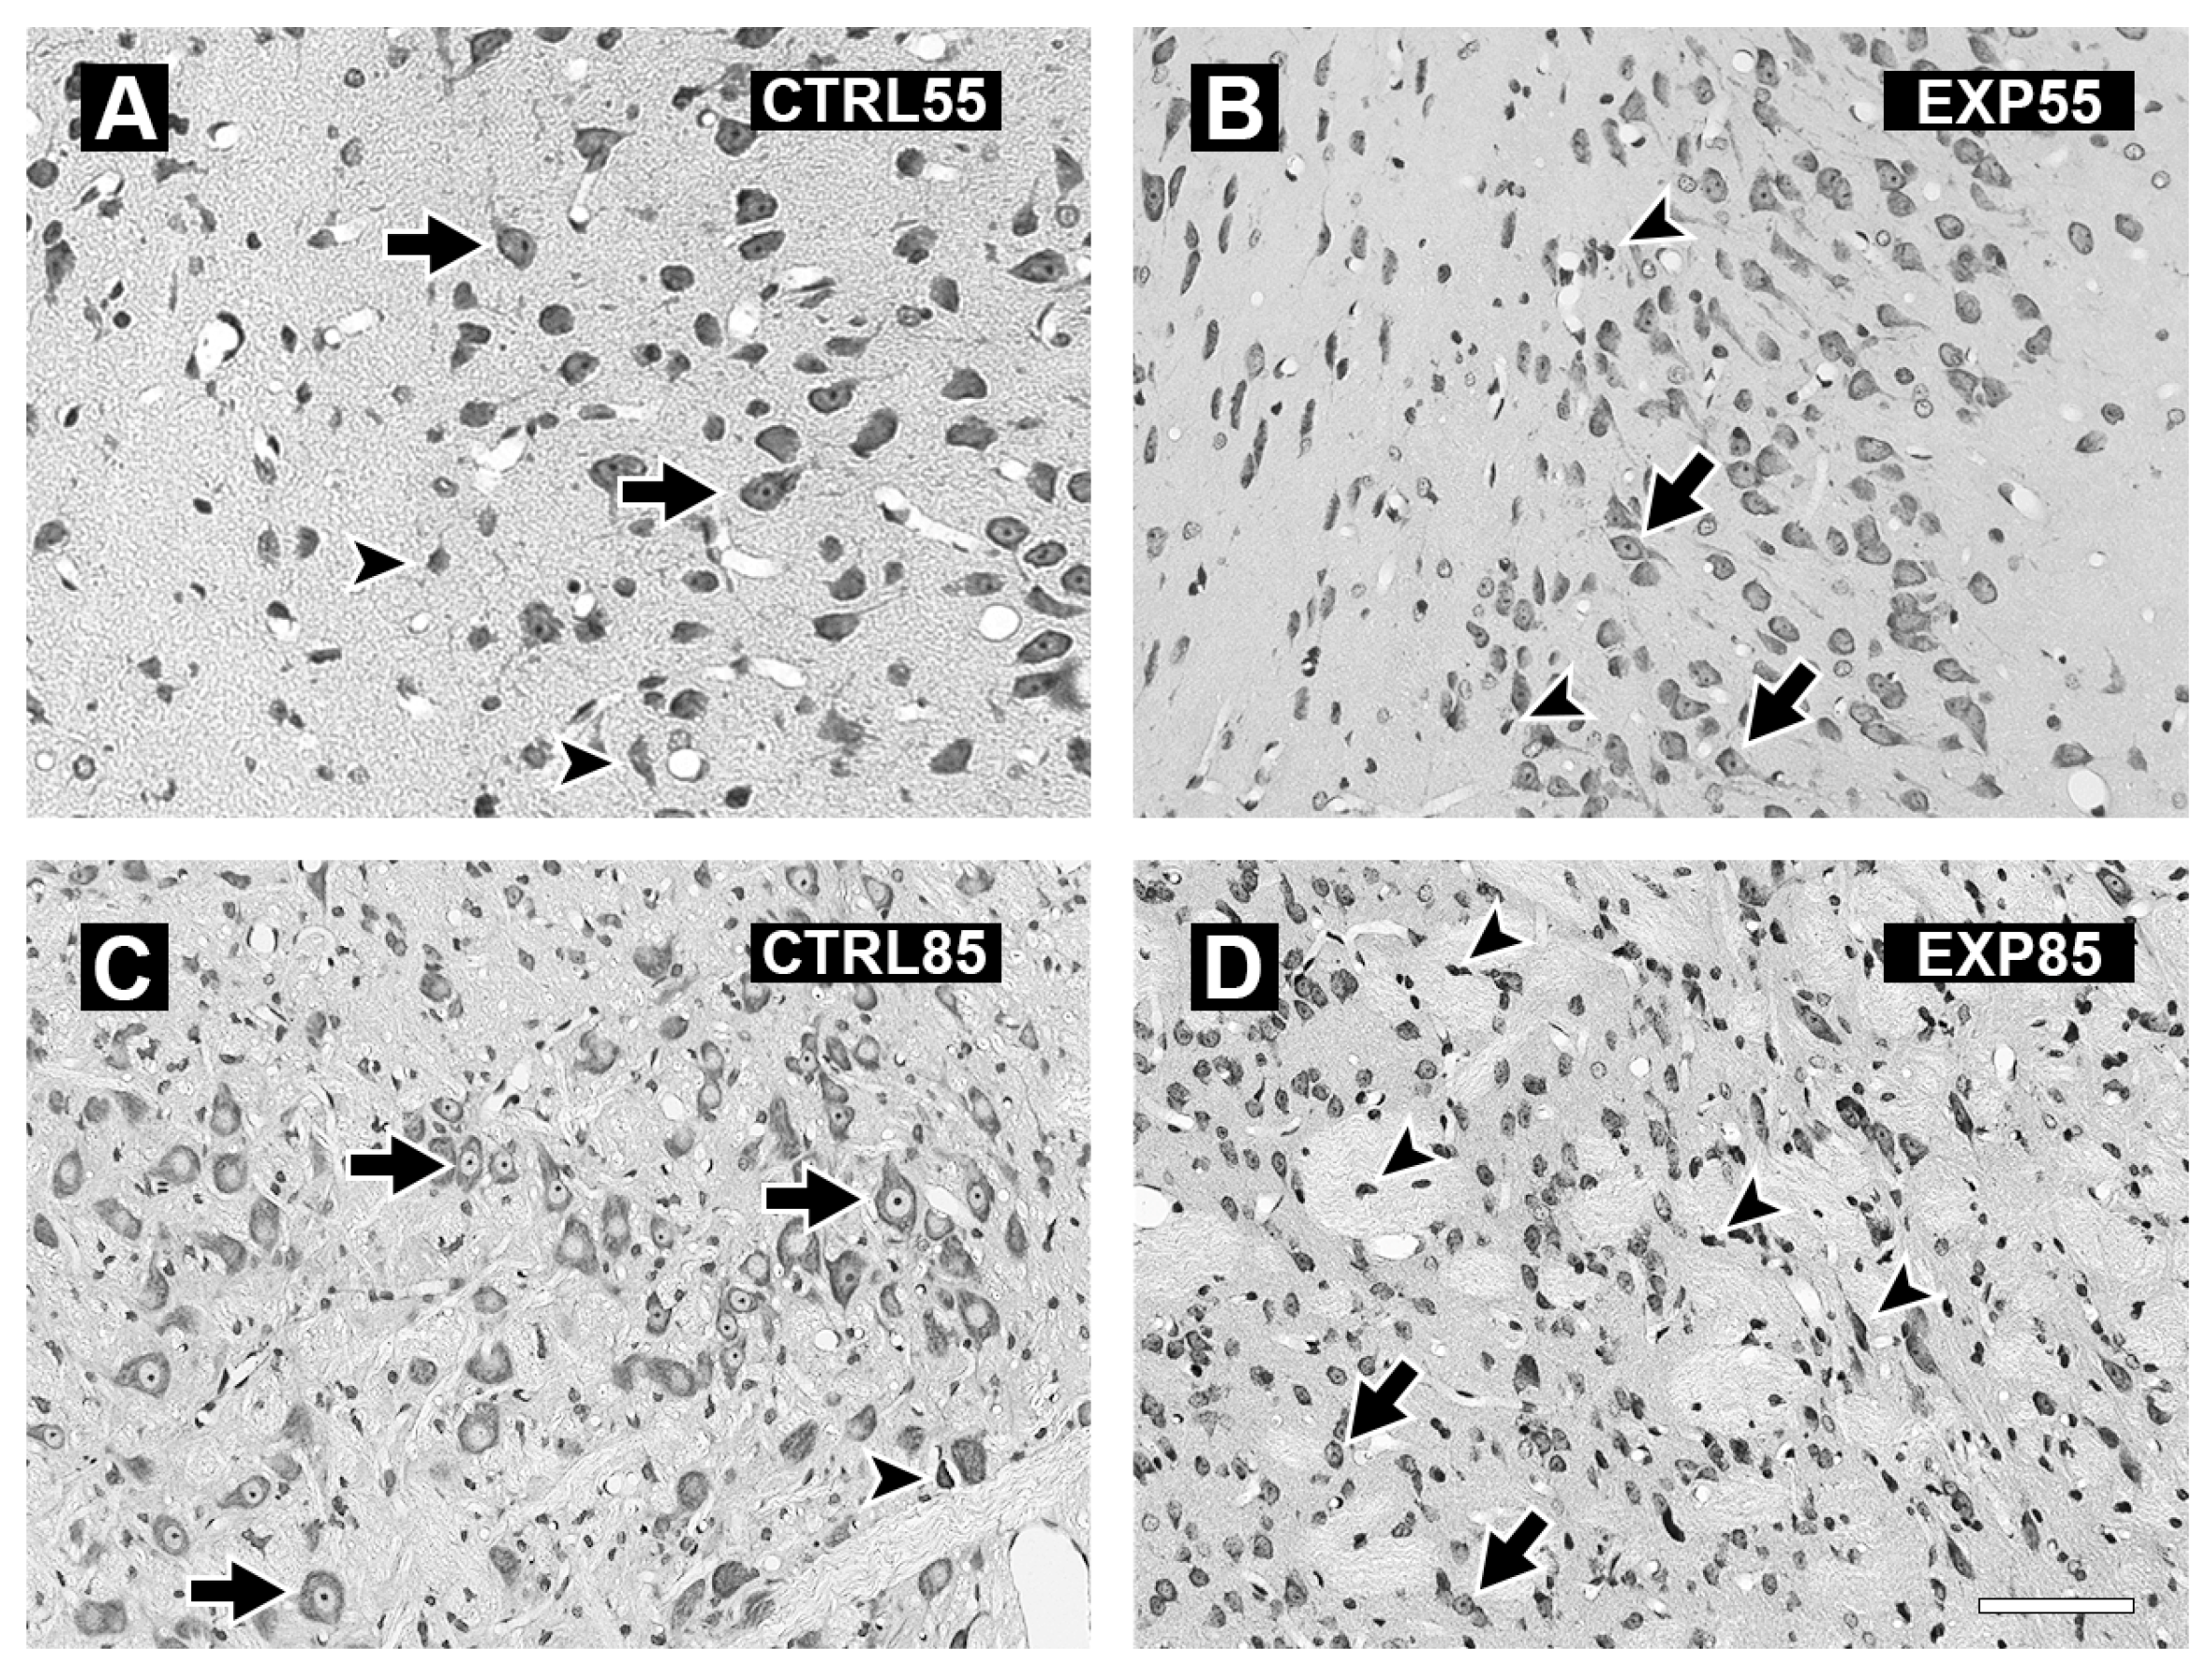

2.3. Histology

3. Results